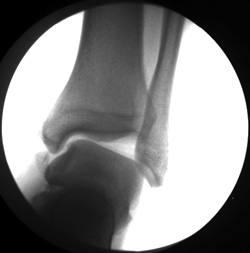

X-rays. X-rays provide images of dense structures, such as bone. Your doctor may order x-rays to rule out a broken bone in your ankle or foot. A broken bone can cause similar symptoms of pain and swelling.

Stress x-rays. In addition to plain x-rays, your doctor may also order stress x-rays. These scans are taken while the ankle is being pushed in different directions. Stress x-rays help to show whether the ankle is moving abnormally because of injured ligaments.

This x-ray shows extreme instability of the ankle.